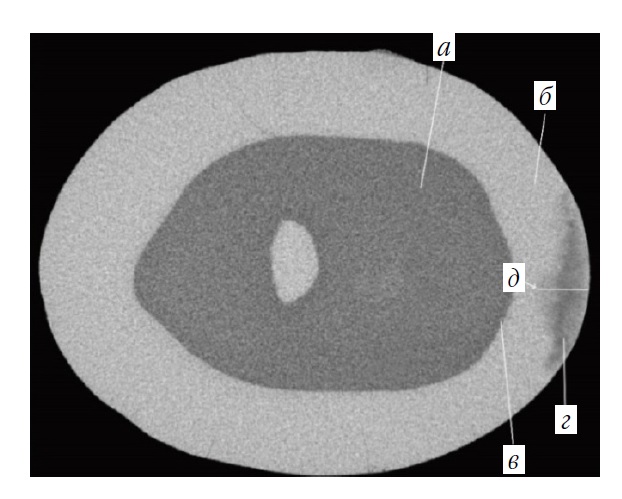

Микро-, мезо-, макроанализ микроструктуры и топологии поверхности эмали в очаге ИКЭ, созданного in vitro по запатентованной технологии, устанавливал её соответствие характеристикам ОДЭ in vivo по данным клинической картины, стереомикроскопии, компьютерной томографии, сканирующей электронной и атомно-силовой микроскопии: код К02.0 по МКБ-10; код 2 по ICDAS; образование на поверхности эмали зоны деструкции с неоднородным, сильно шероховатым рельефом, типичной треугольной формы на шлифах, с толщиной поверхностного слоя 43,1 ± 31,2 мкм и глубиной 423,8 ± 107,4 мкм; наличие рентгенопрозрачных темных участков с неравномерной оптической плотностью и зональным снижением минеральной плотности от 1,47 ± 0,17 – в темной, до 2,03 ± 015 г/см3 – в прозрачной зоне (на 53,1 и 73,4 % от плотности интактной эмали) (рис. 2). Разработанная нами модель экспериментального кариеса соответствовала кариесу эмали in vivo, что предопределяло показания к проведению in vitro инфильтрационного лечения и его модификаций.

Рис. 2. Аксиальный 2D-срез коронки 3.4 зуба, проходящий через зону искусственно созданного кариеса эмали по её максимальной глубине: а – дентин; б – интактная эмаль; в – эмалево-дентинное соединение; г – кариес эмали in vitro с точкой максимальной глубины (д)